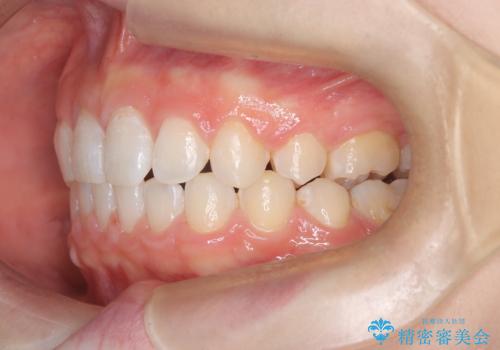

- 右上の八重歯と歯のデコボコ、そして上下の歯の中心(正中)のズレを気にされて来院されました。精密な検査の結果、歯が並ぶスペースが不足しているため、上顎の小臼歯(前から数えて4番目の歯)を抜歯し、そのスペースを利用して歯並び全体を整える治療計画を立案しました。これにより、八重歯の位置を適切に改善し、叢生(歯のデコボコ)を解消するとともに、上下の正中線のズレも改善することを目指します。

今回の矯正治療では、歯が並ぶスペースを確保するため、上顎の小臼歯を抜歯しました。抜歯によってできたスペースを有効活用し、ワイヤーやブラケットを使って右上の八重歯を適切な位置へ移動させ、叢生を解消していきました。また、治療を通じて上下の歯の中心である正中線のズレも改善するよう、慎重に歯を動かしました。治療の結果、長年気にされていた八重歯と歯のデコボコが解消され、上下の正中線も一致。機能的にも審美的にもバランスの取れた、美しい歯並びと笑顔を獲得していただけました。